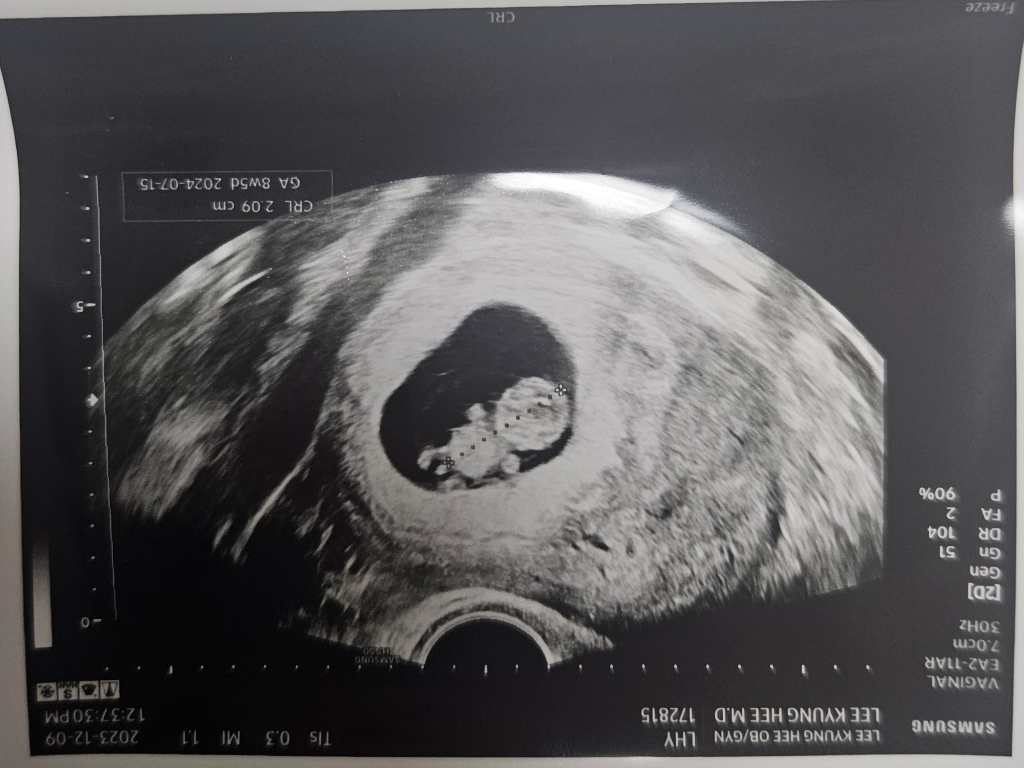

임신 9주차인데 아들같다는데 벌써 성별을 알 수 있나요

9주차인데 아들같다네요 다리사이 저게

혈관이 안보여서 탯줄은 아닌 거 같다고..

벌써 성별을 알 수 있나요?

제가 알기로늘 15주는 되야 안다고 들어서요